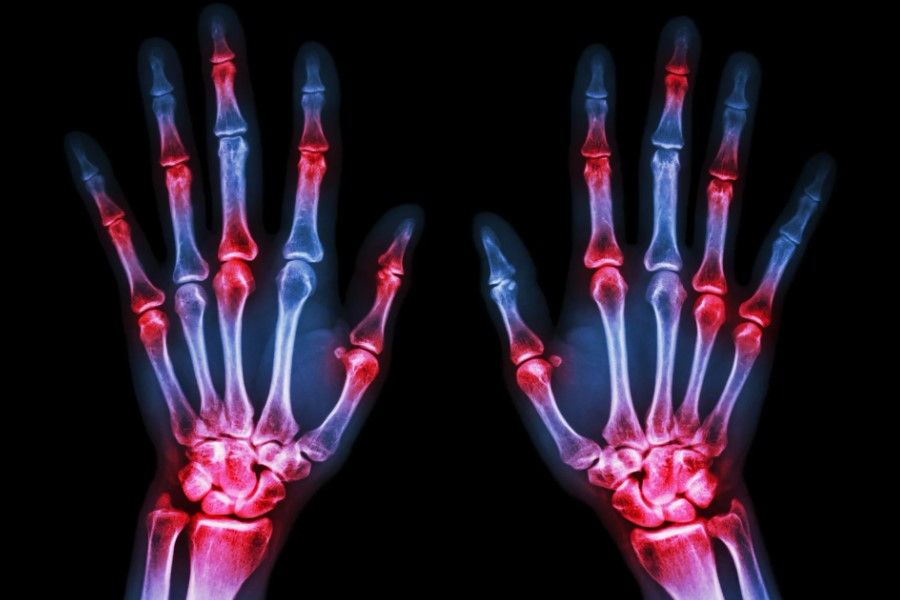

Поліартрит — це запальне захворювання, яке вражає одразу кілька суглобів людини. Не прив’яжете собі до однієї бабусиної казки про ревматизм. Це не просто болить, це може зміни життя. Чому? Та тому що кожен день починається з відчуття, ніби тебе розбирають на запчастини.

- Біль: від легкого вколювання до пекельних мук;

- Набряк: добре, якщо тільки вранці не одягти твої улюблені черевики;

- Скутість: якби тільки герпес був на гантелях;

- Червоність: додає кольору, але не радощів;